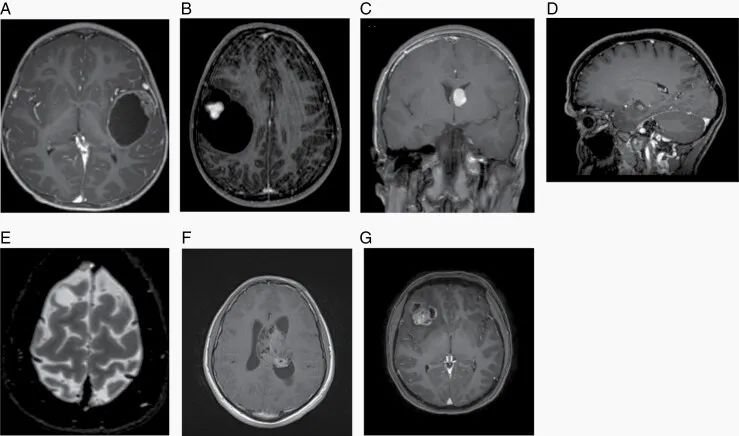

图2:A.毛细胞型星形细胞瘤,T1对比后MRI图像。B.多形性黄色星形细胞瘤,T1对比后MRI图像。C.室管膜下巨细胞星形细胞瘤,T1增强MRI图像。D.神经节胶质瘤,T1对比后MRI图像。E.胚胎发育不良性神经上皮肿瘤,T2加权MRI图像。F.中枢神经细胞瘤,T1对比后MRI图像。G.脑室外神经细胞瘤,T1对比后MRI图像。